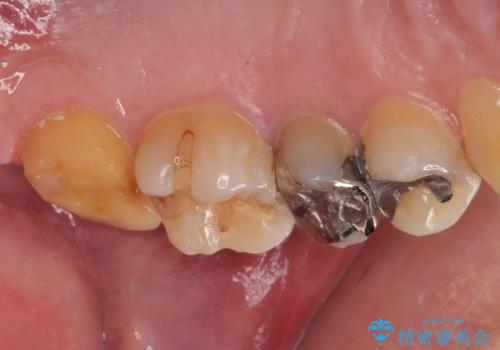

仮歯の状態で1週間ほど過ごしてもらい、歯茎の状態を健全な状態にしてから

歯と歯茎の間に圧排糸と言われる糸を入れてシリコーン印象材にて型どりをしました。

適合もよく、機能的に問題もなく、見た目も満足されていました。

正確な型どりにより再度虫歯になるリスクを低減してくれます。